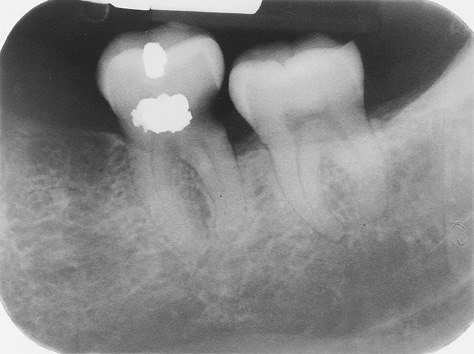

31. What option cannot be selected for the tooth # 3.6?

32. What options cannot be seen in the print of this X ray?

33. What options cannot be seen in the print of this X ray?

34. What option can be selected for tooth # 4.6?

35. What options cannot be selected for the tooth # 1.5?

36. What options cannot be selected for the tooth # 3.7?

37. What options can be selected for tooth # 1.2?

38. What option can be seen in the print of this X ray?

39. What options can be selected for the print of this X ray?

40. What cannot be seen in the print of this X ray?